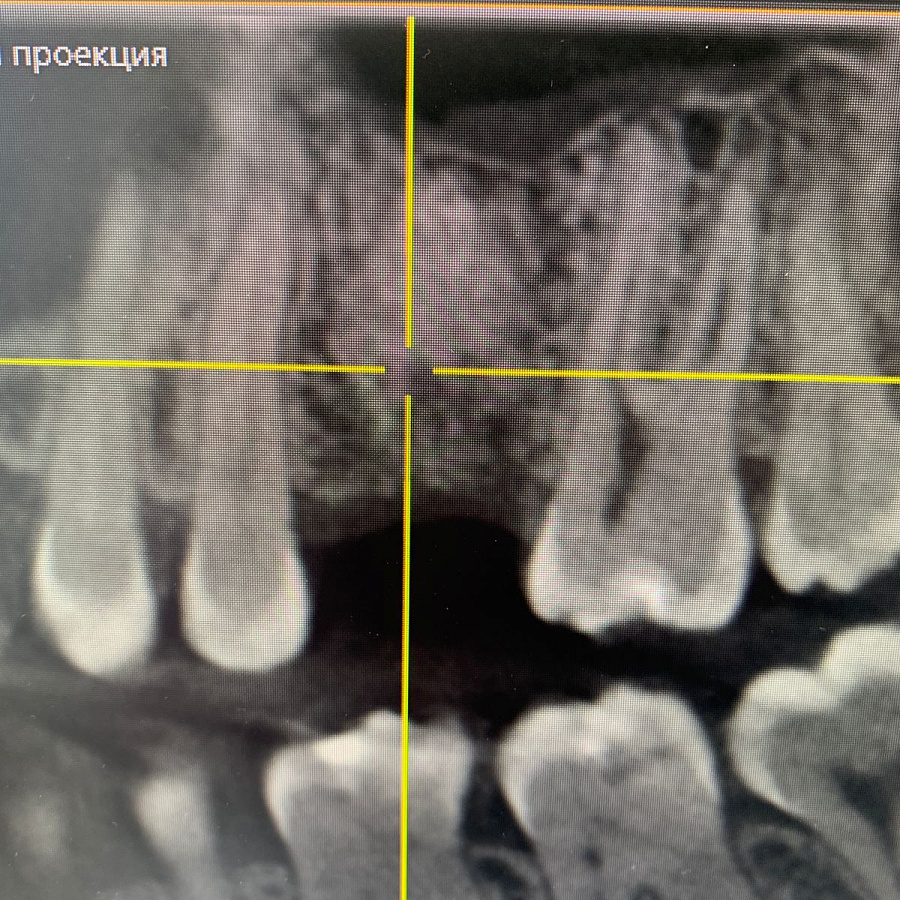

В ходе эндодонтической диагностики доктор обнаружил трещину в корне зуба.

картинка

Этапы лечения

Сохранить или вылечить зуб невозможно, поэтому было рекомендовано удаление зуба с последующей имплантацией.

После удаления таких зубов и извлечения кисты, в кости остаётся большой дефект. Поэтому сделать одномоментную имплантацию зуба, т.е. удаление и имплантацию за один приём невозможно. В таких случаях необходимы дополнительные хирургические манипуляции по подсадке искусственной кости, чтобы сохранить объём костной ткани для последующего протезирования.

Через 6 месяцев после подсадки кости - контрольный снимок и установка зубного имплантата.